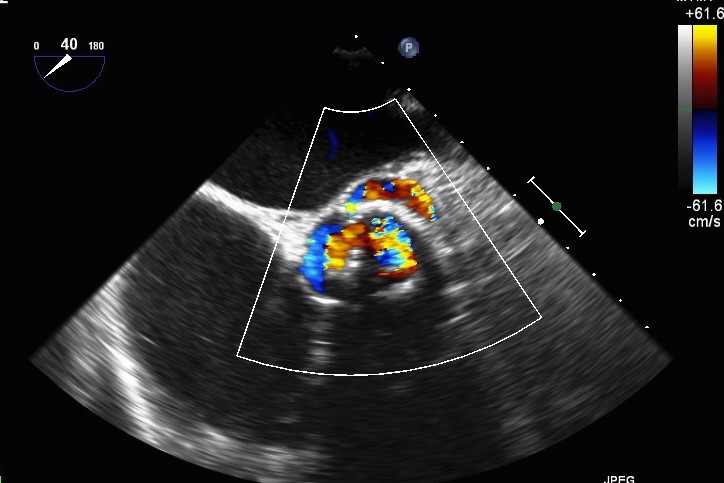

65 years old male with recurrent pulmonary oedema and evidence of surgical bioprosthesis (Perimount Magna n.25, 2008) degeneration consisting of severe stenosis (grad 84/58 mmHg) and severe paravalvular and intraprosthetic regurgitation.

After creating an artero-venous loop between a transeptal and an arterial system, two vascular plugs (AVP III 10×5 and AVP III 8×4 ) were positioned and released, with their final position checked at TEE.